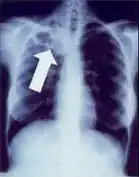

Tuberculosis creates cavities visible in x-rays like this one in the patient's right upper lobe.

A posterior-anterior (PA) chest X-ray is the standard view used; other views (lateral or lordotic) or CT scans may be necessary.

In active pulmonary TB, infiltrates or consolidations and/or cavities are often seen in the upper lungs with or without mediastinal or hilar lymphadenopathy.[1] However, lesions may appear anywhere in the lungs. In HIV and other immunosuppressed persons, any abnormality may indicate TB or the chest X-ray may even appear entirely normal.[1]